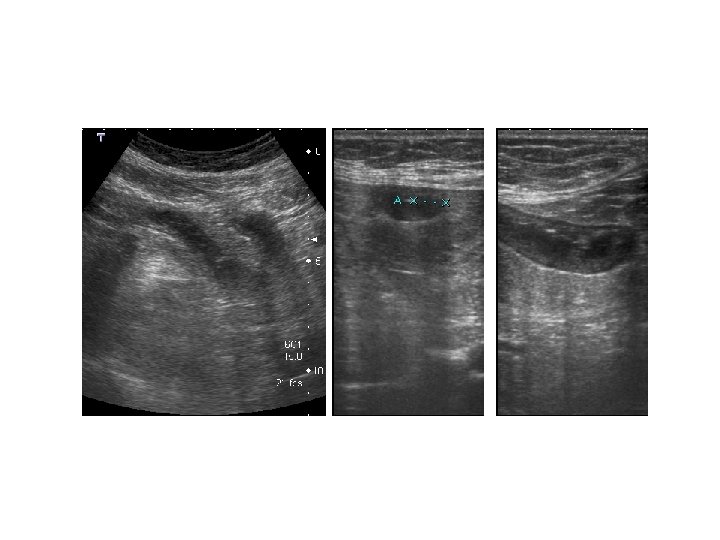

Caso Clínico • Mujer de 82 años, que ingresa de urgencias con el diagnóstico de dolor abdominal, de predominio en FID. • Antecedentes: hipertensión, diabetes, dislipemia. • Se solicita ecografía abdominal. • La solicitud no incluye datos clínicos relevantes, antecedentes ni sospecha diagnóstica.

Informe ecográfico • Largo segmento de asa intestinal de delgado, aperistáltica, edematosa y con engrosamiento transmural, que pudiera corresponder a enfermedad inflamatoria intestinal. • Se aconseja completar estudio ecográfico con TC abdomino-pélvico y tránsito intestinal.